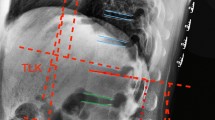

The load carrying capacity (LCC) of the human spine was evaluated in 10 human cadaver spines. The specimens consisted of segments from T11 to S1 with markers placed on the specimens at each vertebral level in both Ap and lateral planes. The specimens were loaded to 1250 N and spinal deflections were recorded and photographed at 125 N intervals during the loading cycle. In 5 specimens, axial and flexion loads were applied to the intact spine. The anterior and middle columns were destroyed in sequence at L2 and the loading process repeated. In the remaining 5 specimens, axial and extension loads were applied with the spine intact and after the posterior and middle columns were destroyed in sequence at L2. Load deflection curves were generated for each test and comparisons were made between intact spines and spines with single and double column destruction. Results: When the axis of loading was anterior to the posterior longitudinal ligament (PLL), destruction of the anterior and middle columns reduced the LCC by 46% and 68% respectively and destruction of the posterior and middle columns reduced the LCC by 30% and 63% respectively. There was minimal change in the LCC when the axis of loading was posterior to the PLL and the anterior and middle columns were destroyed.

Two column destruction of the spine reduced its load carrying capacity for flexion loads by 70%. In thoracolumbar spinal fractures where flexion loads are predominant and anticipated, the authors conclude that surgical stabilisation is indicated with double column failure.